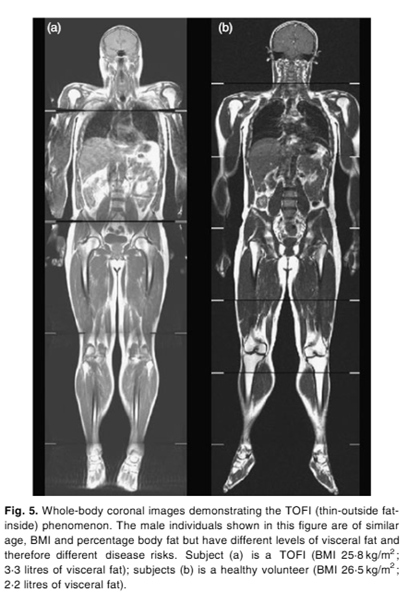

Yukarıdaki görselde ise daha önce bahsettiğimiz TOFI kavramına örnek verildiğini görebiliyoruz. Soldaki birey (a) ile sağdaki birey (b) benzer yaş, BKİ, yağ oranına sahip olmalarına rağmen viseral yağlanma seviyeleri farklı. Soldaki birey, sağdaki bireyin 1.5 katı viseral yağlanmaya sahip ve bu durum çeşitli kronik hastalıklar için daha yüksek riske sahip olduğunu bize düşündürüyor.